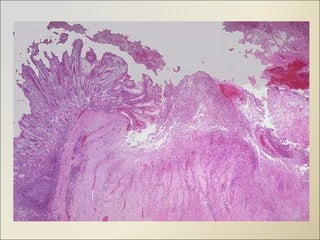

Morphology- Chronic Micr0- 4 Layers Surface debris Neutrophils Granulation tissue Collagen

Morphology- Chronic Micr0-4 Layers Surface debris Neutrophils Granulation tissue Collagen